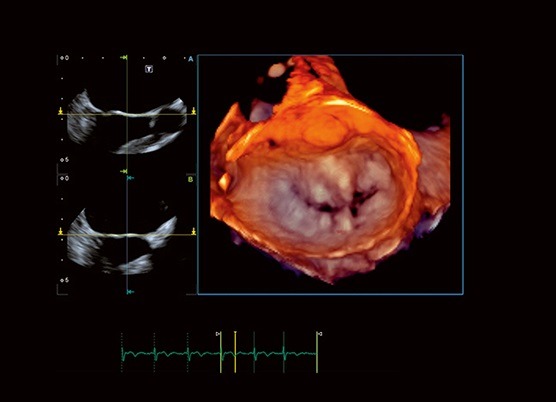

Aplio i900 تصویربرداری چهار بعدی قلب را به روال روزمره کلینیکی تبدیل می‌کند. پروب های تماماً آرایه ای شده، به طور خاصی کوچک و سبک هستند که آنها را ارگونومیک‌ تر و قابل دسترس‌تر می‌کند.

Tissue Enhancement تصاویری با یکنواختی و وضوح حیرت انگیز و نمایش بهبود یافته ای از مرزهای قلبی، بالاخص برای بیماران با شرایط سخت، ارائه می‌دهد.